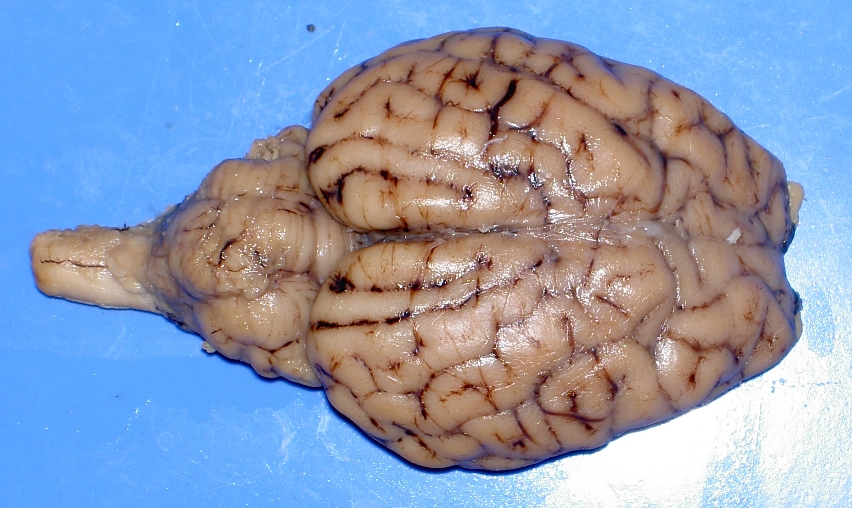

Images of Sheep Brains

These are unlabelled images of sheep brain dissections.

Use them to practice your identification of the listed structures.

5. dorsal view